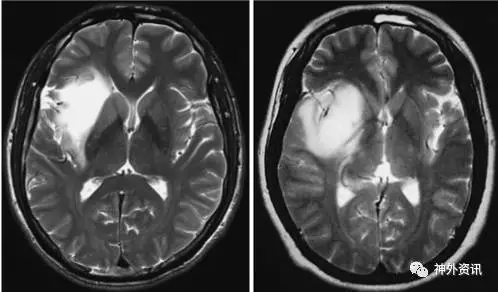

依据术前MRI扫描结果,将岛叶低级别胶质瘤分为累及壳核与未累及壳核两组(图1),应用多元分析模型对比两组患者的预后情况。

图1. 岛叶胶质瘤MRI图像:未累及壳核(左图)和累及壳核(右图)。

研究纳入211例原发性岛叶低级别胶质瘤患者,其中39例(46.9%)肿瘤累及壳核。累及壳核的肿瘤体积大于未累及壳核者(p<0.001),而且较少发生癫痫(p=0.04),累及壳核胶质瘤属野生型IDH1较多见(p=0.003),肿瘤全切的概率也较低(p=0.02)。单变量分析发现,术前KPS≥90分(p=0.007)、肿瘤切除程度高(p=0.008)、未累及壳核(p<0.001)和突变型IDH1(p<0.001)的患者预后明显较好(表1)。多因素分析发现,肿瘤切除程度高(p=0.035)、未累及壳核(p=0.014)和突变型IDH1(p=0.026)的患者预后更好。